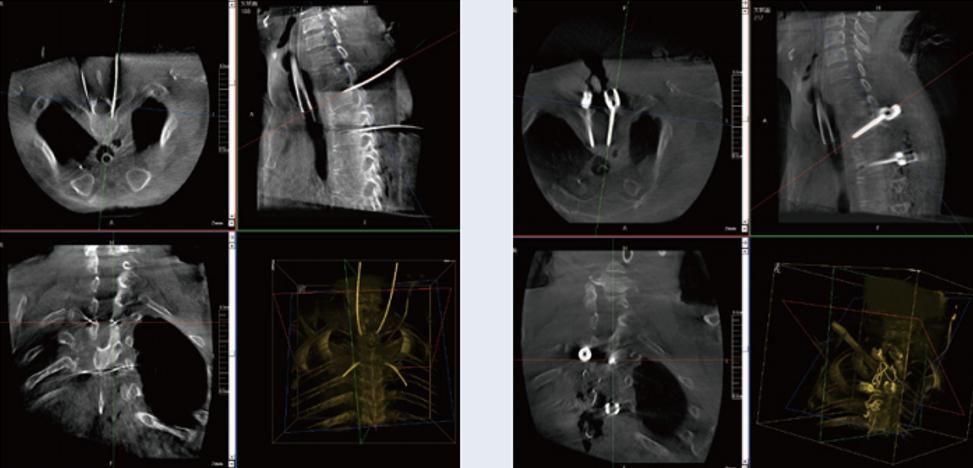

螺釘規(guī)劃后的圖像

植入螺釘后的圖像

術(shù)中三維C形臂與脊柱導(dǎo)航機器人配合應(yīng)用,實現(xiàn)準(zhǔn)確定位,確保了手術(shù)安全、高效完成。術(shù)后二維、三維影像顯示手術(shù)效果良好,達(dá)到預(yù)期目的。

普愛醫(yī)療三維C形臂提供了高質(zhì)量的術(shù)中實時三維圖像數(shù)據(jù),保障了脊柱導(dǎo)航機器人手術(shù)的準(zhǔn)確度和安全性,取得不錯的手術(shù)效果。同時,術(shù)中三維C形臂特有的斷層成像,能幫助醫(yī)生在術(shù)中非常直觀地判斷螺釘植入的準(zhǔn)確度。